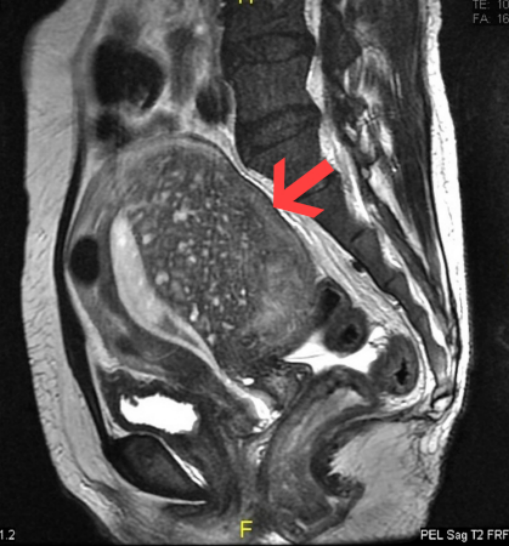

Ultrasound/MRI:

Seeing the uterine myometrium thickening, uneven or localized adenomyoma lesions, etc.